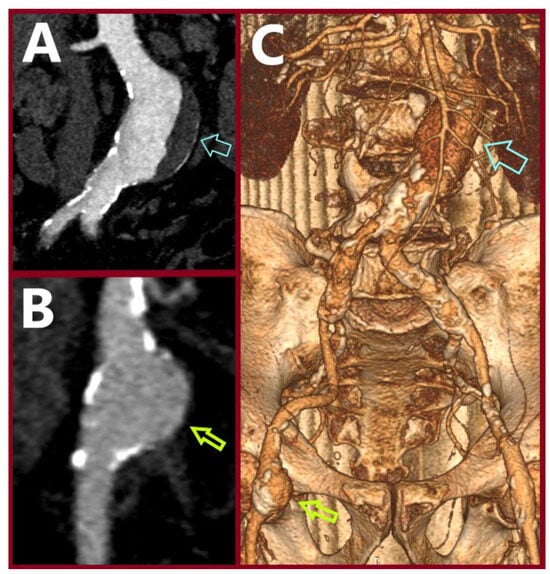

Simultaneous Endovascular Abdominal Aortic Aneurysm Repair and Open Repair of Common Femoral Artery Aneurysm: Short Case Series and Current Review

Background: Common femoral artery aneurysms are rare and are usually associated with aneurysms at other sites, mainly the aorta, iliac, popliteal, superficial femoral, and profunda femoral artery. This combination poses the challenge of synchronous repair for clinically relevant aneurysms. Although endovascular abdominal aortic [...] Read more.

Background: Common femoral artery aneurysms are rare and are usually associated with aneurysms at other sites, mainly the aorta, iliac, popliteal, superficial femoral, and profunda femoral artery. This combination poses the challenge of synchronous repair for clinically relevant aneurysms. Although endovascular abdominal aortic aneurysm repair is the main type of treatment for abdominal aortic aneurysms nowadays, this is not true for common femoral aneurysms, where open repair remains the gold standard. These two distinct operations could be combined in a one-stage procedure when aortoiliac and common femoral aneurysms present simultaneously. This approach potentially saves time and costs, without increasing complications. Methods: A retrospective search was conducted in the Vascular Surgery Department database of a tertiary referral center for vascular surgery, covering procedures from January 2005 to May 2025. Patients were included if they had undergone simultaneous endovascular abdominal aortic aneurysm repair and open repair of a common femoral artery aneurysm. Clinical records, operative details, imaging studies, and follow-up data were reviewed. We additionally provide a literature review regarding this approach. This review additionally incorporates the current knowledge regarding the treatment of common femoral artery aneurysms. Results: Out of 668 endovascular abdominal aortic aneurysm repair procedures, three patients (0.45%) were identified. These three patients were among five patients who were treated for true common femoral artery aneurysm by open repair in the same time interval. All of the patients are currently in good condition without late complications. One patient, who had not performed any follow-up imaging, was diagnosed with large aneurysms at other sites, 10 years later. Conclusions: The combined one-stage endovascular abdominal aortic repair and open repair of a common femoral artery aneurysm by interposition grafting is technically a simple approach that led to satisfactory outcomes. Full article

Show Figures

Figure 1